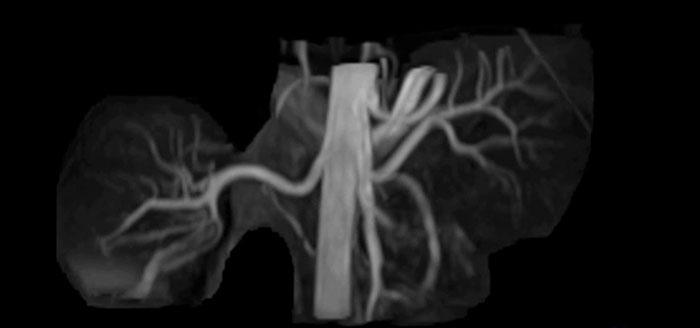

Bildgebung der Nierenarterien ohne Kontrastmittel mit Prodiva 1.5T.